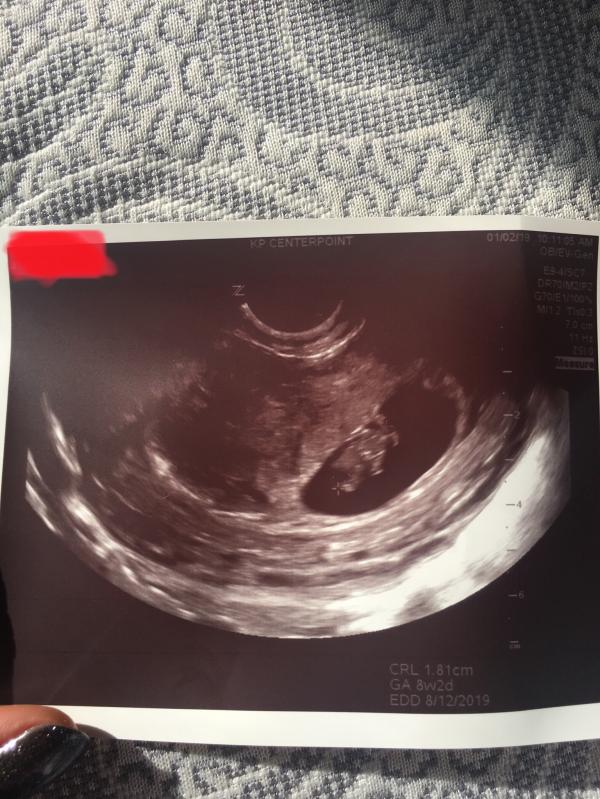

Here’s baby! Measuring 8 weeks 2 days so my due date has changed from 8/11/19 to 8/12/19. Baby has a heart beat and doctor said everything looks well. If you look in the second picture doctor pointed out a second sac. She said it could be a vanishing twin or bleeding. I bled when I was pregnant with my son from 6-10 weeks and so far I’ve had no bleeding or spotting this pregnancy so I’m not worried it’s a hemorrhage. I’m assuming it’s probably just a twin that stopped developing the second sac measured 6 weeks. That has me feeling a little anxious but I’m not going to worry about it! Baby is doing great and measuring perfectly!